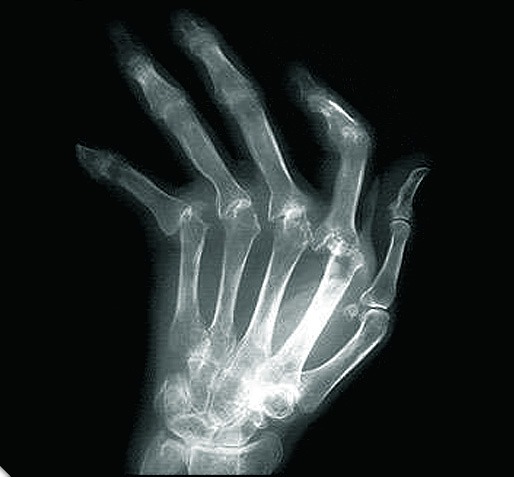

La artrosis es una enfermedad degenerativa causada porel deterioro del cartílago articular, parte que recubre los extremos óseos que unidos dan lugar a las articulaciones, los componentes del esqueleto que permiten el movimiento.

Durante el desarrollo de la enfermedad, la erosión del cartílago articular puede alterar el cartílago articular del hueso opuesto de la propia articulación provocando que comience el mismo proceso de desgaste.

Como consecuencia, puede llegar un momento en el que los cartílagos desaparezcan y aparezca el dolor. A medida que el cartílago va desapareciendo, el hueso reacciona y crece por los lados (osteofitos) produciendo la deformación de la articulación.